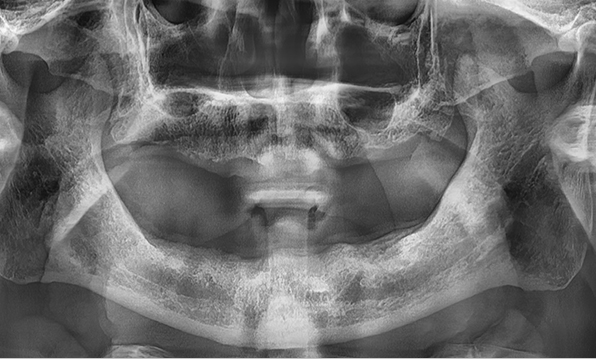

3D 디지털 진단을 통한 체계적인 계획

전체 임플란트는 위턱과 아래턱의 교합, 잇몸뼈의 상태 및

얼굴 변화 등 모든 것을 고려해 식립해야 합니다.

서울더자연치과는 3D 디지털 기술의 정밀 진단을 바탕으로

수술 계획을 세워 수술을 집도합니다.